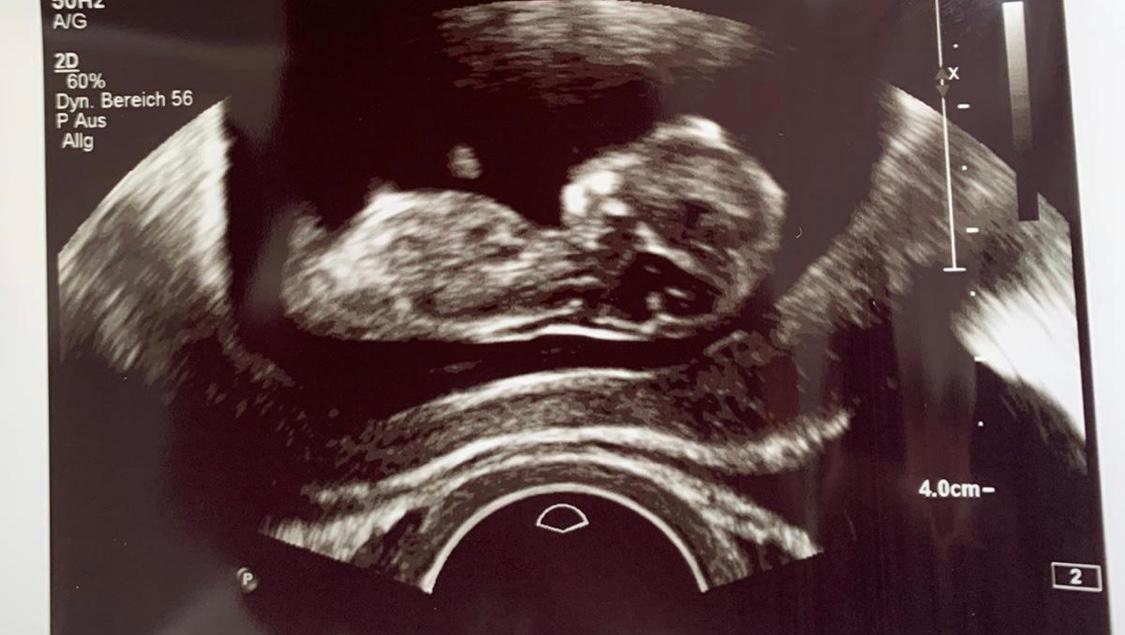

Geschlecht ab SSW 15 sichtbar Im Ultraschall lässt sich das Geschlecht etwa ab SSW 15 erkennen Das aber auch nur, wenn sich das Baby in SSW blickte die Ärztin lange auf das UltraschallGerät, als Svenja fragte, wie es ihrem Sohn ginge ;. 13 SSW Ultraschall Das ist zu sehen Das kleine Wesen wiegt zwischen 14 und 18 Gramm in der 13 SSW Seine Größe beträgt jetzt ungefähr sechs Zentimeter Man kann im Ultraschallbild in der 13 SSW die Rippen, Bein und Beckenknochen erkennen Auch schlucken kann ein Baby in der 13. Hallo ihr lieben ) Ich war heute beim FA und ich bin in der 12 woche plus 6 tage, aufjedenfall hat er versucht das Geschlecht zu erkennen und er meinte als erst sieht nach ein Mädchen aus und dann zack boom meinte er er hätte vielleicht doch ein zipfel gesehen aber er schwankte sehr Meine frage jetzt ist wie sicher sind die Geschlechts erkennung in der 12 fast 13 ssw ?.

Unser Baby in der 13 Ssw ( 124 ) SSL 6,1 cm ( 61 mm ) _____. Ab wann ist das Geschlecht des Baby erkennbar – Das Wichtigste im Überblick bei der Befruchtung entscheidet sich das biologische Geschlecht die Samenzelle bestimmt, ob es ein Mädchen oder Junge wird ab der 13 SSW kann eine kleine Wölbung das Geschlecht vermuten lassen relativ sicher ist ab der 18 SSW das Geschlecht zu erkennen. Unser Baby in der 13 Ssw ( 124 ) SSL 6,1 cm ( 61 mm ) _____.

Schätzungsweise liegen etwa 5 – 10% der Prognosen über Ultraschall daneben Es kann sein, dass dein Baby ungünstig liegt In dem Fall hilft es manchmal, noch einmal aufzustehen und zu laufen Bei der Fruchtwasseruntersuchung kann das Geschlecht über die Erbinformation bestimmt werden Diese Art der Geschlechtsbestimmung ist eindeutig. 13 SSW Man sieht den Kopf des Fötus von oben Die beiden Gehirnhälften (hier eine oben, eine unten im Bild) sind gut zu sehen Sie sind durch eine Mittellinie, das Corpus callosum, getrennt Die Anlagen des Gehirns zeichnen sich deutlich in den Gehirnhälften ab. In Deutschland darf der Arzt das Geschlecht nicht vor der 12 Schwangerschaftswoche verraten – um zu verhindern, dass Babys nur aufgrund des Geschlechts abgetrieben werden Somit bekommen werdende Eltern meist zum zweiten großen Ultraschalltermin (zwischen 180 und 216) mittgeteilt, ob sie einen Jungen oder ein Mädchen erwarten.